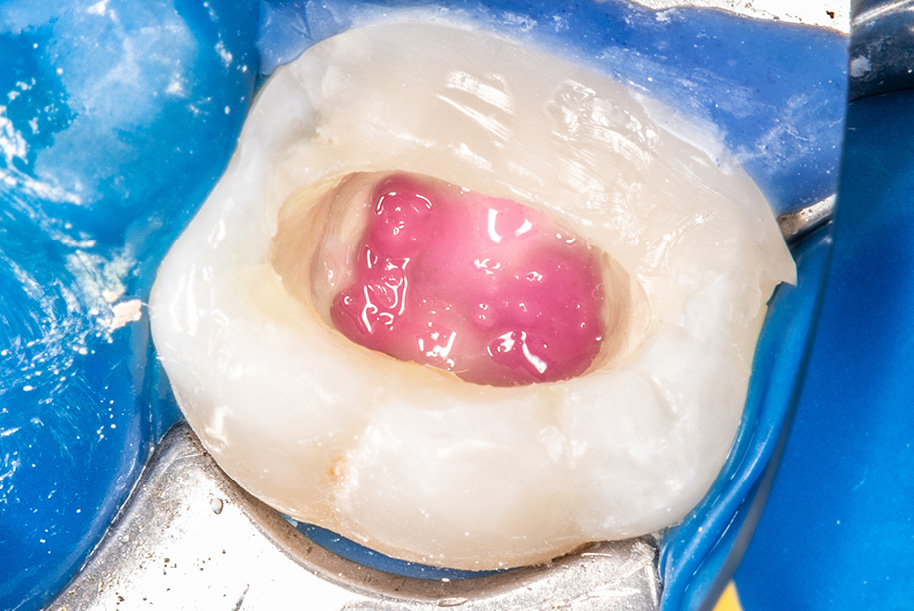

Leczenie endodontyczne to jeden z częściej wykonywanych zabiegów w praktykach stomatologicznych. Procedury, które muszą zostać wykonane, to właściwa diagnoza stanu miazgi i tkanek okołowierzchołkowych, identyfikacja ewentualnych przeszkód, następnie opracowanie i dezynfekcja systemu kanałowego zakończone szczelną obturacją i odbudową zęba [1, 2]. Najczęstszą przyczyną patologii miazgi jest próchnica, rzadziej są to: urazy zębów, pęknięcia rozległe, preparacje pod uzupełnienia bezpośrednie lub pośrednie [3]. Długoterminowe powodzenie w leczeniu endodontycznym to najważniejsze kryterium oceny trafności diagnostyki oraz wykonanych procedur. Wybór metody odtwórczej zdaje się być jednym z kluczowych czynników decydujących o utrzymaniu prawidłowej funkcji zęba [1, 4, 5]. Sposób odbudowy jest determinowany przez ilość tkanek, które muszą zostać odtworzone po zakończeniu leczenia kanałowego. Procedura wykonania dostępu [...]